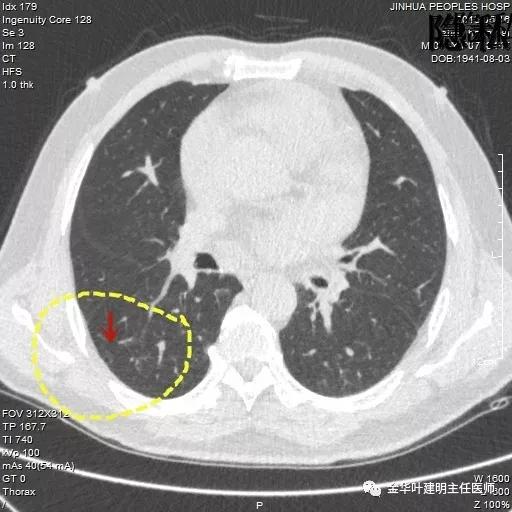

金华的周某,今年已经78岁了,上个月底单位退休人员体检,查出他的右肺有一结节,结果出来后,这个月通知他到胸外科复诊。因为是我的亲戚,便直接找到了我,我从电脑里调出他的CT片,如下所示:

可见其右下叶有一空腔性病灶,壁薄,病灶下方见到实性密度的成份。我们看过目前的片子后,马上想到的是此病灶以前有没有,对比是非常重要的。调出之前片子: